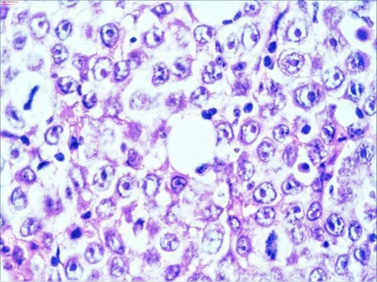

The macroscopic pathology analysis revealed hemorrhagic elevations of the ileal mucosa with infiltrating lesion of the intestinal wall and luminal stenosis in up to 90%. The same was spreading in the mesenteric fat. Microscopic view showed 4–5 mitoses on large microscopic field (Figure 7).

28.jpg 29.jpg

Figure 7. HE staining